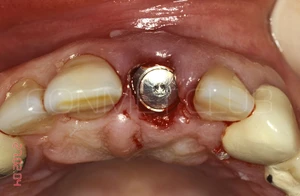

Через 3 месяца временная коронка удалена и начато изготовление стандартной металлокерамической коронки. Вид на имплантат КОНМЕТ сразу после удаления временной коронки.

Из-за глубокого резцового перекрытия пришлось сильно утачивать стандартный, прямой абатмент. Безусловно не самая простая ортопедическая ситуация с сложно прогнозируемым сроком службы.